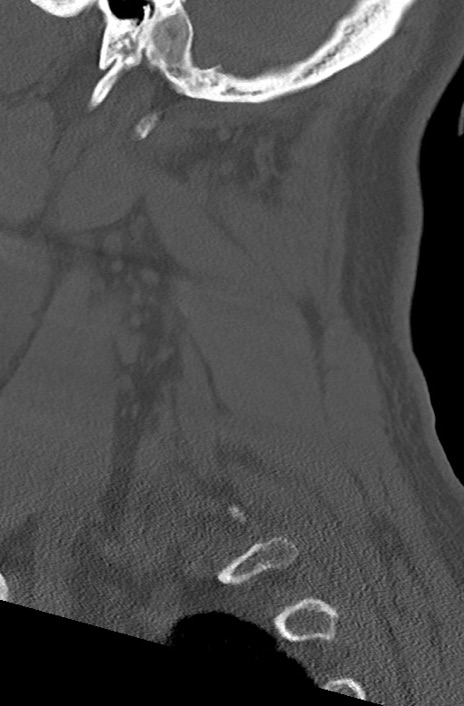

頚椎CT

冠状断像